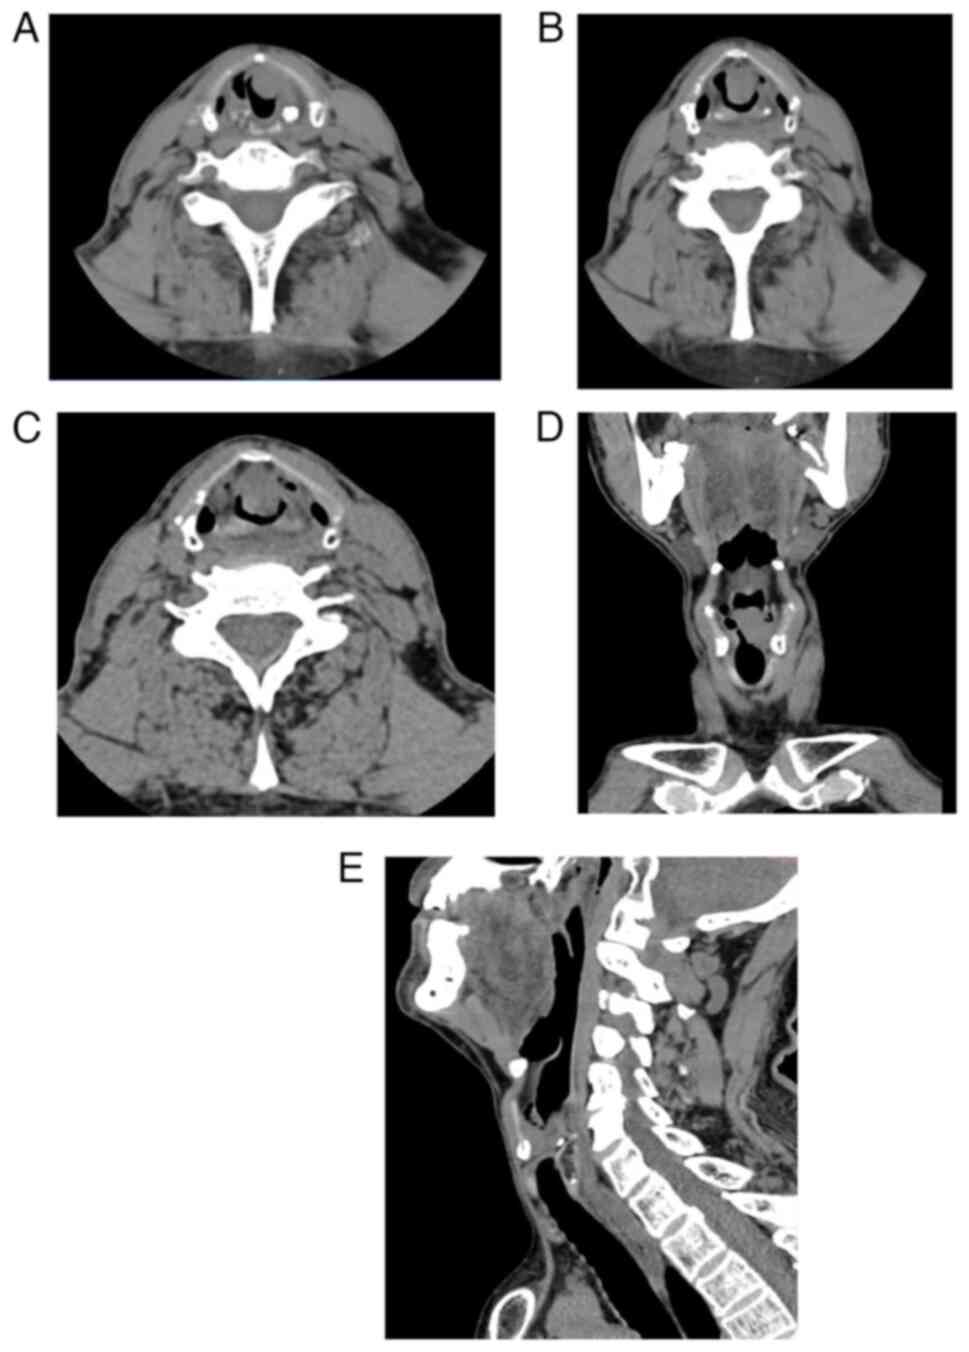

Therefore, the patient was first subjected to throat spiral computed tomography. The results revealed a tumor mass of ~1.9×1.7 cm2 in size (Fig. 1A-E). Additionally, as shown in Fig. 1D and E, complete obstruction at the glottis level in the larynx was observed, which directly resulted in the patient's sudden onset of upper airway obstruction prior to hospital admission. In addition, laryngoscopy followed by biopsy was performed at the tumor site. Laryngoscopic images were captured at 1 month and 1 day prior to surgery. The tumor displayed a polypoid growth pattern, occupying a substantial portion of the glottis with localized expansion, smooth surface and absence of evident ulceration or secretion (Fig. 2A and B).

Figure 1.

Larynx spiral computed tomography scans of the patient at 1 month prior to surgery. (A) Horizontal image 1. (B) Horizontal image 2. (C) Horizontal image 3. (D) Coronal image. (E) Sagittal image.